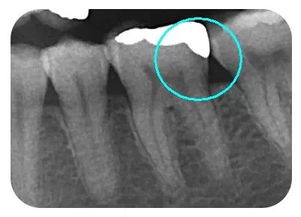

嵌體位于牙體內部,只能修復缺損的牙體組織,不能保護剩余的牙體組織。

嵌體在咬合受力后會(huì )將力傳導至洞的側壁,在剩余牙體內產(chǎn)生拉應力,過(guò)大的拉引力會(huì )造成牙體折裂。 要避免咬硬物,注意勿進(jìn)食過(guò)硬食物,以免因給牙齒帶來(lái)過(guò)大的負荷而影響嵌體的長(cháng)期使用。

嵌體位于牙體內部,只能修復缺損的牙體組織,不能保護剩余的牙體組織。嵌體在咬合受力后會(huì )將力傳導至洞的側壁,在剩余牙體內產(chǎn)生拉應力,過(guò)大的拉引力會(huì )造成牙體折裂。

要避免咬硬物,注意勿進(jìn)食過(guò)硬食物,以免因給牙齒帶來(lái)過(guò)大的負荷而影響嵌體的長(cháng)期使用。而且應禁止吸煙、少喝酒,煙酒會(huì )對牙齒和周?chē)恼衬そM織造成刺激和傷害,加大牙齒周?chē)椎陌l(fā)生幾率,所以患者在生活中最好做到不吸煙和少喝酒。